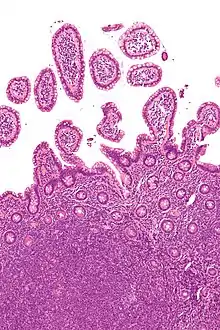

Micrograph showing mantle cell lymphoma (bottom of image) in a biopsy of the terminal ileum. H&E stain. | |

The history and physical examination may reveal some of the signs and symptoms consistent with Mantle Cell Lymphoma. Biopsy of the involved tissues (such as the lymph nodes, bone marrow, gastrointestinal tract, spleen or other areas) shows the characteristic histopathologic changes of MCL. There are distinct growth patterns of MCL seen on biopsy; these include the diffuse type, nodular type, mantle zone lymphoma and in situ mantle cell lymphoma.[7] In the diffuse growth pattern, there is a diffuse growth of lymphoma cells throughout the lymph node resulting in effacement of the architecture of the lymph node.[7] In the nodular type, there are large nodules of MCL cells in the lymph node with no germinal centers observed.[7] In MCL with expansion of the mantle zone, the lymphoma cells cause expansion of the mantle zone around normal germinal centers.[7] And in MCL in situ, the lymphoma cells are contained within the mantle zone without expansion.[7] Histologically, the lymphoma cells in classic MCL are characterized as small to medium lymphocytes with scant cytoplasm and clumped chromatin with prominent nuclear clefts and the nucleoli are not visible.[7] There are cytologic subtypes; the blastoid subtype, is characterized by round nuclei, fine chromatin with some distinct nucleoli.[7] The pleomorphic subtype is characterized by nuclei that vary in size and shape with some having a cleaved form.[7] The blastoid and pleomorphic subtypes of MCL are associated with a more aggressive course.[7]